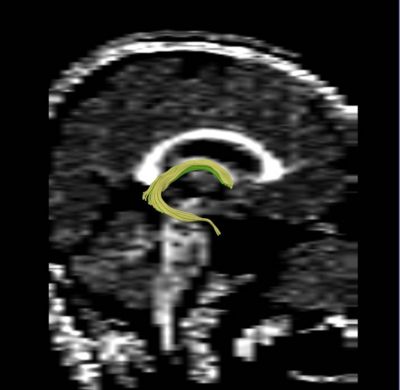

We apply fiber tractography to quantify fornix Fractional Anisotropy (FA) in schizophrenia. Two ROI method (shown in the figures) were used to extract left and right fornix in 34 chronic schizophrenia subjects and 40 matched controls, and mean FA along the entire tract was extracted separately for the left and the right sides and compared between groups. Preliminary data indicate bilateral decreased FA in the fornix of schizophrenics.

ROIs for Tractography

Fornix roi1.jpg Fornix roi2.jpg

Example Fornix Tractography

Fornix tracts.jpg